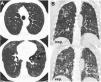

La TC torácica en espiración es una técnica complementaria de la inspiración que aporta valiosa información fisiológica y puede ser más sensible que las pruebas de función respiratoria para detectar atrapamiento aéreo. Tiene múltiples indicaciones, entre las más frecuentes están la enfermedad obstructiva de la vía aérea producida por bronquiolitis obliterante, asma, síndrome de Swyer-James, traqueomalacia, neumonitis por hipersensibilidad o sarcoidosis. En alguna de ellas, como la bronquiolitis obliterante, la TC espiratoria puede ser la única técnica de imagen que detecta alteraciones en las fases iniciales. Si queremos que sea de utilidad diagnóstica, hay que asegurarse de que el estudio tenga calidad suficiente. Para ello se recomienda explicar al paciente en qué consiste la prueba, emplear instrucciones precisas y realizar un breve entrenamiento antes de iniciar la adquisición. En este trabajo sugerimos estrategias para optimizar la técnica y proponemos un algoritmo para interpretar los hallazgos radiológicos en el contexto de la patología obstructiva pulmonar.

Expiratory CT scan is a complementary technique of inspiratory CT that provide valuable physiological information and may be more sensitive to detect air trapping than pulmonary function tests. It is useful in many obstructive airway diseases, including obliterative bronchiolitis, asthma, Swyer-James syndrome, tracheomalacia, hypersensitivity pneumonitis and sarcoidosis. In obliterative bronchiolitis, expiratory CT scan may be the only imaging technique that shows abnormalities in the early phase of disease. In order to obtain a good quality study, we should explain the procedure to the patient, use precise instructions and do some practice before image acquisition. Here we describe strategies to optimize the technique and propose an algorithm that help in interpretation of imaging findings in patients with obstructive airway disease.